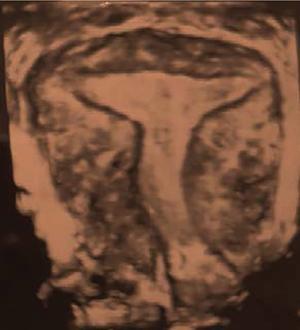

MÜLLERIAN DUCT ANOMALIES Rajani Gorantla Müllerian ducts are a pair of tubular structures that give rise to uterus, cervix, fallopian tubes and upper two-thirds of vagina. Disruption or failure of normal development can result in occurrence of Müllerian duct anomalies (MDAs). These are commonly associated with other congenital anomalies of urinary tract and ovaries due to the close relationship between the development of mesonephric and paramesonephric ducts; few patients also have associated skeletal system anomalies. The prevalence of MDAs in an unselected population was 5.5%; 8% among the infertile women, 12.3% in women with a history of recurrent pregnancy loss and 24.5% in women with miscarriage and infertility. Most of the patients with MDAs are asymptomatic and found incidentally on imaging for any other gynaecological problems, in evaluation of a patient with renal, skeletal or abdominal wall abnormalities. In symptomatic women, complains are related to the type, severity, obstructive anomaly or nonobstructive anomaly. The symptoms can be obstetric or gynaecological related, includes recurrent spontaneous abortions, infertility, preterm labour, intrauterine growth restriction and abnormal foetal lie. Few adolescent girls may present with primary amenorrhoea, hypomenorrhoea, abnormal vaginal bleeding, cyclical pain and mass. Rarely they can present with pelvic inflammatory disease with abnormal vaginal discharge, dyspareunia and urinary tract infections. The female reproductive system develops from a pair of Müllerian or paramesonephric ducts, urogenital sinus and vaginal plate. The ovaries develop separately from the primordial ridge. It is of great importance to understand the normal stages of development, as failure or interruption of any of these stages can lead to a simple to complex spectrum of anomalies. The three stages of Müllerian duct development include: At 6–10 weeks of gestation age, two paired Müllerian ducts and Wolffian ducts formation occurs. When Y chromosome factor (testicular determining factor) is absent, the Wolffian ducts undergo degeneration. The Müllerian ducts further elongate caudally and cross the Wolffian ducts to fuse in the midline. At 10–13 weeks of gestation age, caudal and lateral fusion of the two Müllerian ducts forms primitive uterovaginal canal, which is possessed of solid tissue initially located side by side and further internal canalization leads to the formation of two channels/canals divided by a septum. At this stage, there is reabsorption of the caudal septum and forms single cervical canal and vagina lumen. In around 15–20 weeks of gestation age, complete resorption of the septum takes place in a caudocranial direction from the isthmus to fundus and development of single endometrial cavity results. The fused caudal part of Müllerian ducts gives rise to the uterus, cervix and upper two-thirds of vagina; the unfused cranial part forms the fallopian tubes (Fig. 11.14.1.1). The lower vagina develops from the urogenital sinus, which is separated from the rectum by urorectal septum around 7 weeks of gestation age. The primitive uterovaginal canal embeds into the dorsal wall of urogenital sinus and forms Muller’s tubercle. Around 13 weeks of gestation, two solid masses known as sinovaginal bulbs originate from the upper part of the Muller’s tubercle, further proliferate into the caudal end of the uterovaginal canal to become a solid vaginal plate. Later canalization or degeneration of the central cells of the vaginal plate forms the lower vagina, which is usually completed by 20 weeks’ gestation. The vertical fusion of the upper and lower vagina occurs with resorption of tissue in between and forms single vaginal cavity (Fig. 11.14.1.2). The vaginal lumen is separated from the urogenital sinus by the hymenal membrane. Just before birth, the hymen normally ruptures due to retrogression of the central epithelial cells. However, a thin fold of mucous membrane persists around the vaginal introitus. The ovaries develop separately from migration of primordial germ cells to the genital ridge. Ureteric buds develop separately and concurrently. So renal anomalies are most commonly associated with MDAs with an association of 30%–50%. Various classification systems have been proposed over the past several decades to describe MDAs. Ideally, same classification system needs to be followed by a gynaecologist, surgeon and radiologist for better communication. Buttram and Gibbons classification was suggested in 1979, and it was based upon the level of failure in normal development and segregate the anomalies into groups with similar clinical manifestations, treatment, and prognosis for foetal salvage. According to Buttram and Gibbons, the uterine anomalies were classified into six classes as described in Table 11.14.1.1. The drawback is the lack of classification of vaginal and other anomalies separately. The ASRM (previously the American Fertility Society – AFS) classification system is the most widely accepted classification worldwide over the past years and was introduced in 1988. According to this classification, MDAs are classified into seven classes (class I to class VII) as mentioned in Table 11.14.1.2. However, several limitations have been described by Grimbizis and Campo in 2010 (Fig. 11.14.1.3). The drawbacks of the ASRM classification system are as follows: Hence in 2016, an updated classification of uterine septum, that is ASRM-2016 was proposed and officially approved morphometric criteria are given for distinguishing between septate, normal/arcuate and bicornuate uteri (Table 11.14.1.3). The VCUAM classification was proposed in the year 2005. The main concern is to provide a simple, systematic, clinical classification in addition to providing a precise reflection of the entire malformation. The female genital organs were divided into the following subgroups in accordance with the anatomy: vagina (V), cervix (C), uterus (U) and adnexa (A). Associated malformations were assigned to a subgroup (M) relative to each specific organ. The disadvantage is due to its inherent complexity, and more than 56,700 individual combinations of anomalies are possible. ESHRE and ESGE established a common working group named CONgenital UTerine Anomalies (CONUTA) in order to devise an improved classification system (Table 11.14.1.4). It was published in 2013. Anatomy is the basis for systemic categorization of the MDAs. The subclasses are divided by the different degrees of uterine deformity and their clinical significance (Fig. 11.14.1.4). Cervical and vaginal anomalies are classified into independent supplementary subclasses (Figs. 11.14.1.5–11.14.1.6). For most of the clinicians, it helped as starting point for the development of guidelines for their diagnosis and treatment. The malformations are graded according to severity, U0–U5, C0–C4 and V0–V4, with U5, C4 and V4 being more severe. Class U3 incorporates bicorporeal fusion defects (didelphys and bicornuate) as this was considered as a more functional mode of classification. Arcuate uterus was not included separately, but this is categorized under normal variant into class U1c. Recent studies have demonstrated that the ESHRE/ESGE system provides an effective and comprehensive classification for almost all the currently known MDAs and overcomes the limits of previous classifications. However, there is a relative overdiagnosis of septate uterus with the application of ESHRE–ESGE criteria has been reported and which potentially might lead to unnecessary surgical overtreatment. C0 C1 C2 Normal cervix Septate cervix Double ‘normal’ cervix C3 C4 Unilateral cervical aplasia Cervical aplasia U4 V0 V1 V2 V3 Normal vagina Longitudinal nonobstructing vaginal septum Longitudinal obstructing vaginal septum Transverse vaginal septum and/or imperforate hymen V4 Vaginal aplasia C MDAs’ characterization and classification is of great significance, as the treatment is determined by the type and severity of abnormality. The various imaging modalities available include: HSG was the most recognized imaging modality, earlier to the development of the ultrasonography (USG) and MRI. It is an invasive fluoroscopic-guided procedure for uterine and tubal assessment, and is performed during the midproliferative phase of the cycle, ideally between days 7 and 10 of the cycle when endometrium is thin. Fluoroscopic spot images obtained to evaluate uterine configuration, uterine filling defects and fallopian tube patency. HSG allows evaluation of only the component of the uterine cavity that communicates with the cervix. The anatomic information about myometrium and external fundal contour will not be provided by HSG. The diagnostic criteria used to diagnose MDAs on HSG include: HSG findings of different MDAs are described in Table 11.14.1.5 and Fig. 11.14.1.10. Virtual HSG is a noninvasive technique performed by using a computed tomography (CT) scanner, done 45 s after the contrast material instillation begins. Contraindications are similar to those for HSG and include pregnancy and active pelvic infection. There is no necessity for retraction of the uterus or manipulation of the cervix. The procedure is quick, easy and prophylactic administration of antibiotics is not required. The use of a power injector helps to ensure a steady low pressure of instillation. The procedure is less painful, more comfortable and easily tolerated by patients than conventional HSG. Radiation exposure sometimes requires cervical clamping, which may result in complications such as bleeding and infection. Transabdominal pelvic ultrasound can diagnose uterine anomalies with accuracy rate of 47%. Two-dimensional transvaginal ultrasound (TVUS) has high sensitivity and specificity than transabdominal study and provided some information about external and internal fundal contours. The detection rate is high if the scan is performed in secretory phase due to better visualization of endometrium. Three-dimensional USG shows great accuracy than 2D USG in evaluation of the uterine morphology. The technique of 3D USG varies with different vendors. It displays both the external and internal fundal contours and lower uterine segment by acquisition of single coronal view of uterus (c-view) (Fig. 11.14.1.11). The only disadvantage is that it is transvaginal study and shall not be done in paediatric age group and sexually inactive women. Three-dimensional TVUS has become the first line of screening tool in most of the infertility clinics as it is noninvasive, faster, repeatable, allows storage of volume data and has multiplanar capability for systematic evaluation of the uterine and cervical cavities. The salient features of various Müllerian anomalies on 3D USG are described in Table 11.14.1.6 with images. Three-dimensional ultrasound is combined with sonosalpingography in this technique and provides better delineation of the uterine morphology. It is a less invasive procedure done in proliferative phase with instillation of saline into the uterine cavity and assessment of the uterus will be done. MRI is a universally accepted imaging modality in the documentation of MDAs and accuracy rate of 100% have been reported. MRI provides excellent delineation of both the internal and external uterine anatomies. T2-weighted (T2W) images are the mainstay of pelvic imaging and are performed without fat suppression. T1-weighted (T1W) images are mainly for the haemorrhagic content. The disadvantages of MRI include time-consuming procedure, not cost-effective, large body habitus, pacemakers, recent surgical history and claustrophobia. The current and proposed MRI protocol given by the European Society of Urology (ESUR-MRI protocol) intends a dedicated evaluation of MDAs as mentioned below (Fig. 11.14.1.12): Vaginal anomalies can be accurately diagnosed with the prior administration of the ultrasound gel, to distend vagina (Fig. 11.14.1.13). It will help in better diagnosis of complex vaginal anomalies, like vaginal septations or vaginal duplication. The normal MRI appearance of uterocervical canal and vagina are shown in Fig. 11.14.1.14. Uterine aplasia/hypoplasia/agenesis is class 1 MDA according to ASRM classification and U5 uterine anomaly according to ESHRE classification. It is a formation defect of the paramesonephric ducts with complete or segmental agenesis of uterus and vagina. The incidence rate is around 10%–15% of all MDAs and considered as the most severe form of uterine anomaly. Most of them have complete uterovaginal agenesis with no single completely developed uterine cavity and are associated with Mayer–Rokitansky–Küster–Hauser syndrome (MRKHS). Two types of this syndrome are depicted. The typical form or type A represents the absence or remnants of the uterus, cervix, upper two-thirds of vagina with normal ovaries and fallopian tube (Fig. 11.14.1.15). The atypical form or type B is associated with the abnormalities of the ovaries, fallopian tubes and genitourinary system (Fig. 11.14.1.16). In a few cases (approximately 10%), unilateral or bilateral uterine remnants and with or without endometrial cavity will be seen (Fig. 11.14.1.17). Most of them present with primary amenorrhoea due to complete uterovaginal agenesis and manifest as MRKHS. These patients have normal secondary sexual characteristics due to the preserved normal ovarian function and phenotype. If uterine remnants with functional cavity is present, will present with cyclical pain along with amenorrhoea due to cryptomenorrhoea and haematometra. USG is the first modality for identification of these anomalies, absence of uterus with normal ovaries is diagnostic. But, it is difficult to locate the uterine remnants and cavity due to small acoustic window. MRI is the gold standard and it classifies into uterovaginal agenesis and hypoplasia. If hypoplasia is identified, sagittal and axial sections are taken. These remnants are seen as T2 hypointense tubular structures, located in close relation to ovaries in the adnexa. Once we identify the uterine remnants, it is important to look for the functional endometrial cavity. These will have reduced endometrial and myometrial width. MRI can easily delineate the zonal anatomy due to its high soft tissue contrast resolution. The management of Müllerian agenesis consists of counselling for the patient and her parents. Some patients with MRKHS opt for creation of neovagina for normal sexual life. Various techniques are available. In the presence of a functional Müllerian remnant, regardless of whether it is communicating or not, medical suppression of menses can be initiated and should be followed by laparoscopic removal of the hypoplastic remnant. Unicornuate uterus or hemiuterus is defined as the unilateral uterine development and the contralateral Müllerian duct could be either partially formed or absent. It is a formation defect and the necessity to classify it in a different class than that of uterine agenesis, which is also a formation defect, is due to the existence of a fully developed functional uterine hemicavity. It is considered as class II anomaly according to ASRM classification and class U4 according to ESHRE classification. The frequency rate is around 20% of MDAs. Renal anomalies most often occur in association with unicornuate uterus and usually on the same side of uterine agenesis. Further unicornuate uterus is divided into two subclasses depending on the presence or absence of a functional rudimentary cavity in ESHRE classification: In ASRM classification, unicornuate uterus is divided into four subcategories: Mostly asymptomatic and presence of the noncommunicating uterine remnants will be identified at the time of infertility work up or caesarean section. If a functional cavity is present, the presentation is dysmenorrhoea or haematometra in an adolescent. The common obstetrics-related complications include abnormal foetal lie, intrauterine growth retardation, preterm delivery, placental abnormalities and uterine rupture. Gynaecological complications are ectopic pregnancy and endometriosis due to retrograde menstruation. On imaging, unicornuate uterus is seen as tubular and fusiform or banana-shaped structure at paramedian location, the endometrium is narrow and tapers to the apex with normal myometrial anatomy and reduced uterine volume. The rudimentary cavity or remnants are better depicted on 3D USG (Fig. 11.14.1.18) and MRI. However, MRI is superior to USG due to its high soft tissue resolution. The rudimentary cavity can communicate with main cavity or connected by fibrous band. The nonfunctioning cavity will be seen as T2 hypointense structure with loss of zonal anatomy (Figs 11.14.1.19 and 11.14.1.20), whereas the functioning cavity will show the deformed zonal anatomy (Fig. 11.14.1.21), and its complications like haematometra as T1/T2 hyperintense endometrial collection. Unicornuate uterus without rudimentary cavity does not require any procedure. But in the presence of communicating or noncommunicating rudimentary horn, surgical resection must be considered to prevent complications. Uterine didelphys is a class III MDA based on the ASRM classification and class U3b bicorporeal uterus according to ESHRE classification with an incidence rate of 5% among the uterine anomalies. It is a lateral fusion defect; results from complete failure of the Müllerian duct fusion. Two noncommunicating endometrial cavities with preserved zonal anatomy are seen with separate cervix. According to ESHRE classification, it is defined as external fundal indentation completely dividing the uterine corpus up to the level of external cervical os. It is most commonly associated with longitudinal vaginal septum in around 75% of cases. Some patients may show transverse vaginal septum and these will be obstructive or nonobstructive type. Renal anomalies are also commonly associated with uterine didelphys. Uterine didelphys is usually asymptomatic and diagnosed incidentally on pelvic examination or caesarean section. The uterine didelphys with obstructed vagina (Fig. 11.14.1.22) will present at adolescence as dysmenorrhoea, haematometrocolpos and haematosalpinx. Sometimes retrograde menstrual flow can cause endometriosis and pelvic adhesions. Obstetric-related complications include abortion/foetal growth restriction and poor pregnancy outcome. The uterine didelphys with obstructed hemivagina due to transverse vaginal septum and associated ipsilateral renal agenesis are the manifestations of the syndrome called obstructed hemivagina and ipsilateral renal agenesis anomaly/Herlyn–Werner–Wunderlich (HWW) syndrome (Fig. 11.14.1.23).